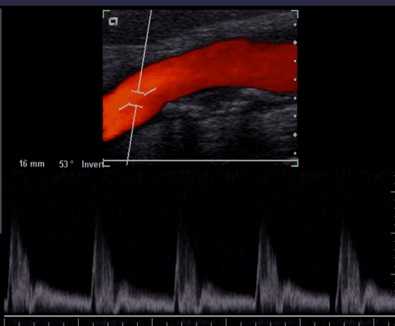

D型(多普勒型)超声诊断

多普勒超声诊断主要分为图谱多普勒、彩色血流成像、彩色能量成像。其中,以彩色血流成像最常见。

测量血流的三种方法:

一、连续波多普勒(CW)

连续发射和接收脉冲波,多普勒超声束内的所有回波信号都被记录下来,显示的频谱是声束通道上所有血流信息的混合血流频谱。

优点:可测量高速血流,定量分析血管狭窄、反流和分流性病变。

缺点:缺乏距离选通能力,不能定位诊断、探头敏感性低。

二、脉冲波多普勒(PW)

采用了距离选通(也称距离分辨,为了获得某一深度的血流信息,只接收在某一距离上的回波信号)方法。

优点:能沿超声束的不同深度对某一区域的多普勒信号进行定位检测。

缺点:脉冲重复频率的上限受最大探测深度的制约。

脉冲重复频率(PRF):每秒钟发射的脉冲群的数目,是衡量PW的一项重要参数。